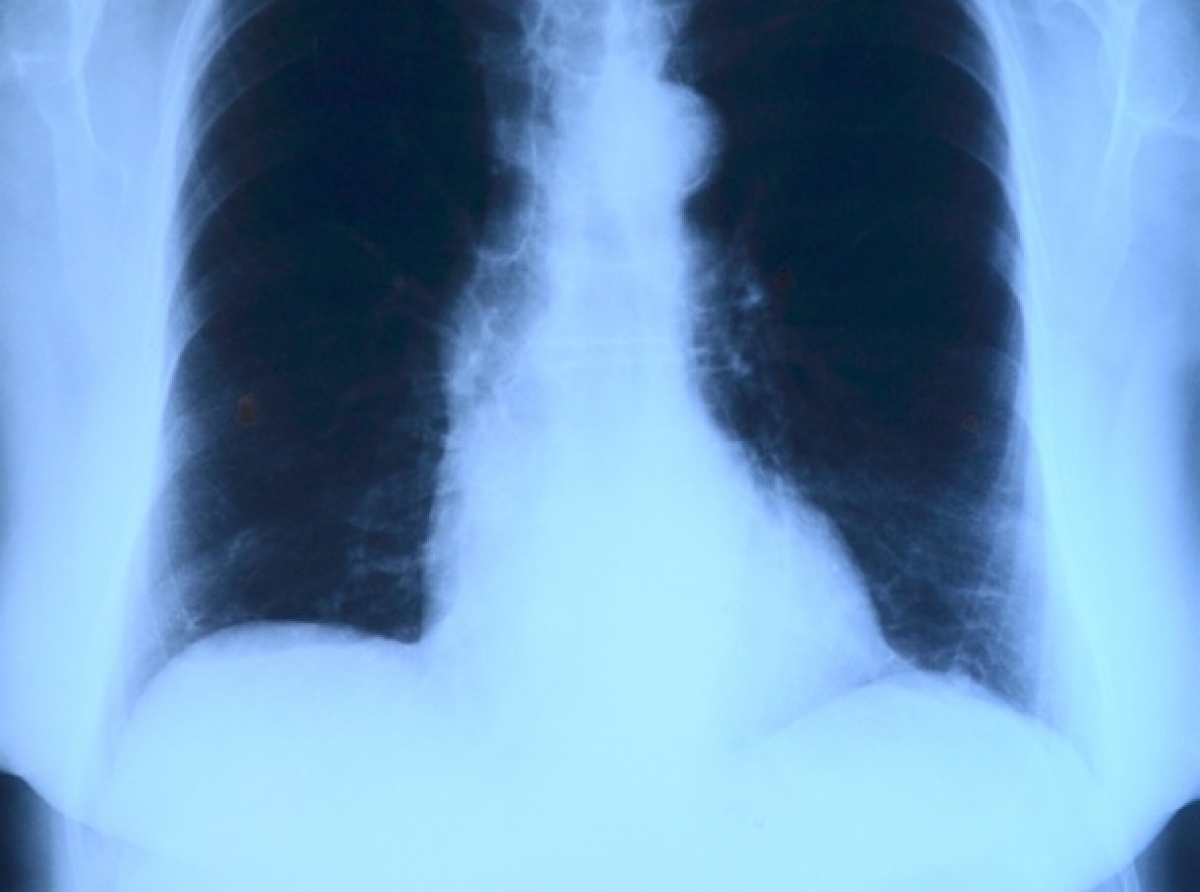

В ходе надзорных мероприятий городской прокуратурой были установлены 13 местных жителей, освобожденных в 2019 году из мест лишения свободы и до сих пор не прошедших обследования. Понуждать их пройти флюорографическое обследование на предмет наличия туберкулеза пришлось через суд.